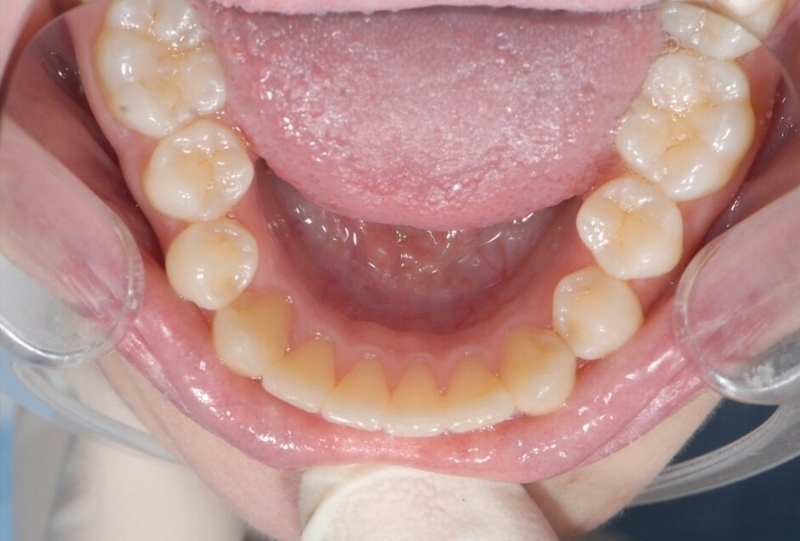

Cas 2 - Orthodontie par aligneurs invisibles

Avant

Après